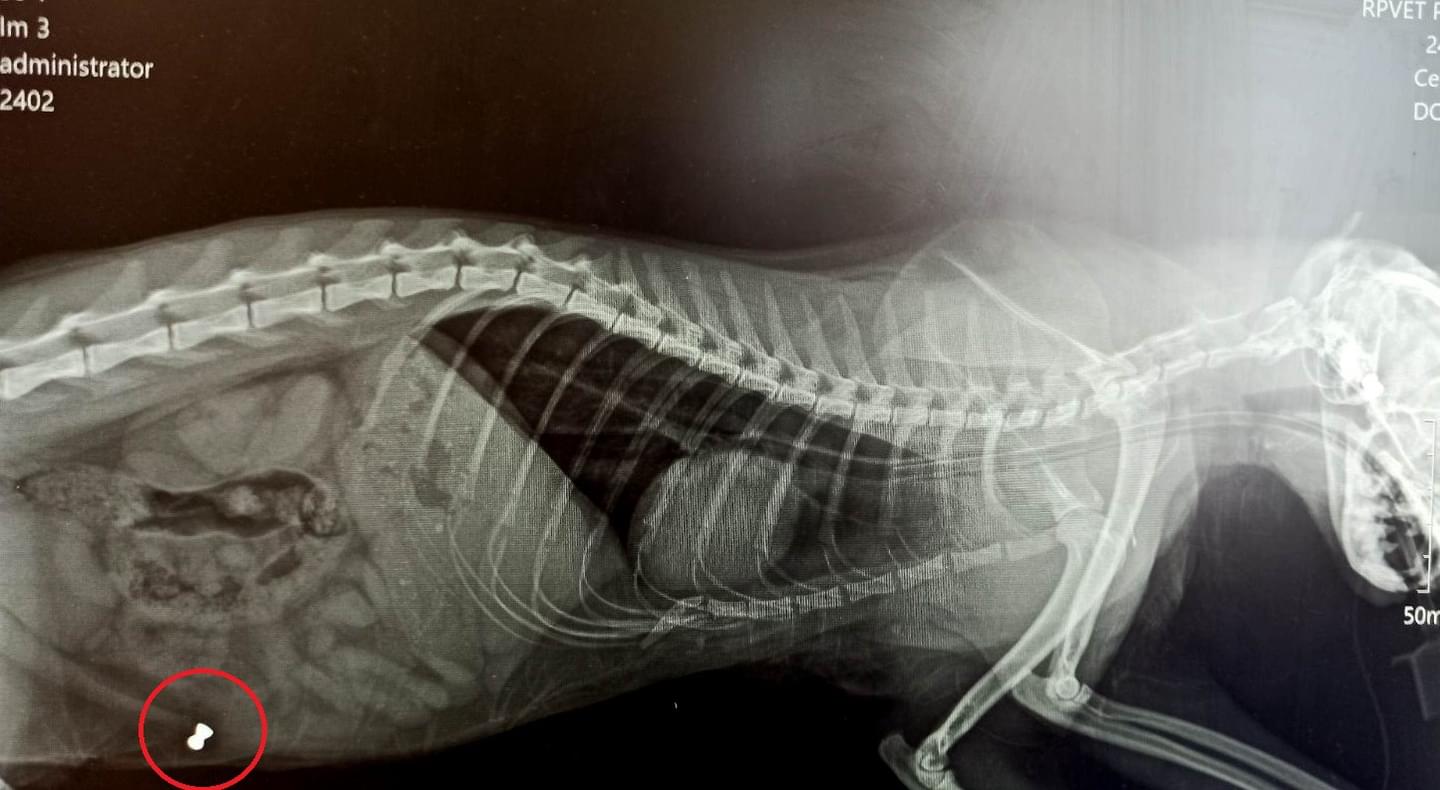

Při vyšetření bylo zjištěno, že Cecilka nejenže přišla o oko následkem střely ze vzduchovky, která jí navíc uvízla v lebce, ale další projektil pak rentgen ukázal ještě v oblasti břicha zvířátka.

Cecilka byla operována, nyní se ze svých zranění zotavuje doma, ale z útoku zatím neznámého střelce si bohužel ponese doživotní následky.